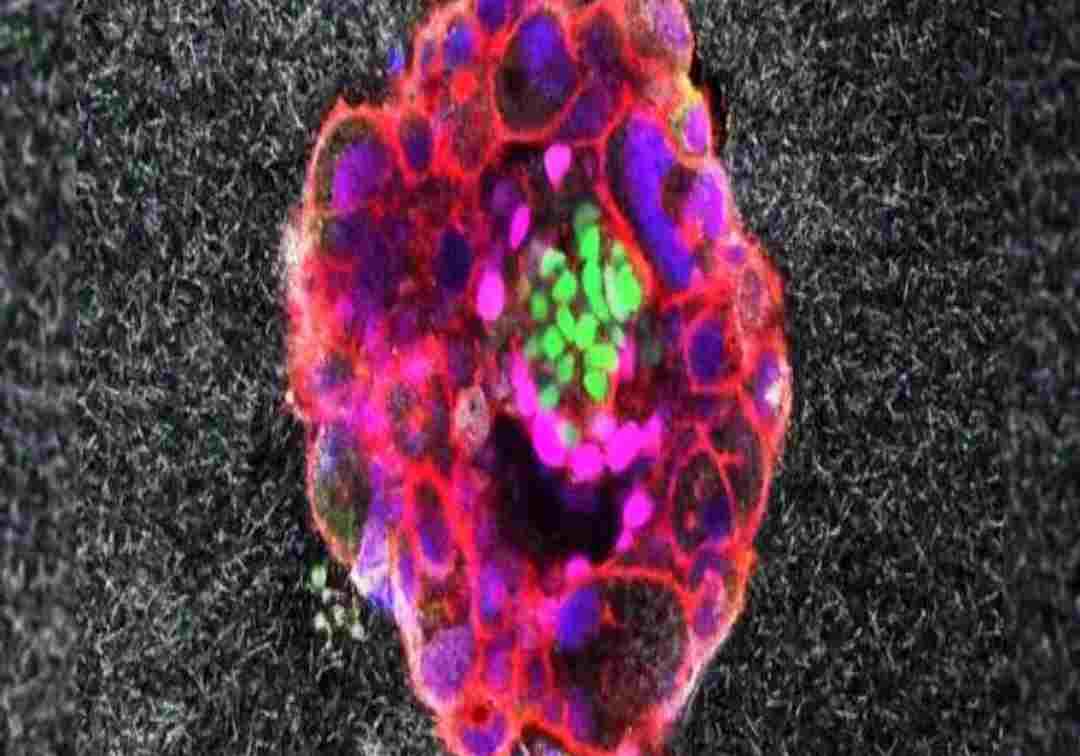

IVF వంటి సంతానోత్పత్తి చికిత్సల సక్సెస్ రేటును మెరుగుపరచడంలో వైద్య పరిశోధకులు మరో ముందడుగు వేశారు. మునుపెన్నడూ లేని రీతిలో మానవపిండాన్ని గర్భాశయంలోకి ప్రవేశపెట్టే పద్ధతిని త్రీడీలో చిత్రీకరించారు.

ఆ రియల్ టైమ్ ఎలా సహాయపడుతుందో పరిశోధకులు విశ్లేషించారు. బార్సిలోనాలోని డెక్సియస్ యూనివర్శిటీ హాస్పిటల్ డోనేట్ చేసిన కృత్రిమ పిండాలను ఉపయోగించి ఈ ప్రయోగాన్ని విజయవంతంగా పూర్తి చేశారు.